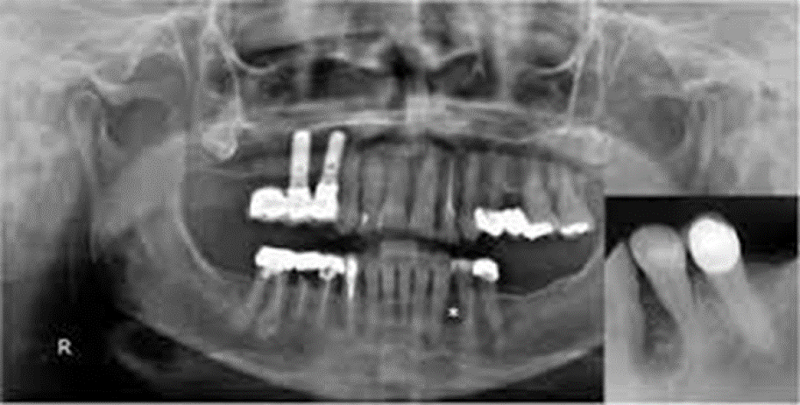

{"name":"Oral Path ID Chapter 6-9", "url":"https://www.quiz-maker.com/QPREVIEW","txt":"This condition is linked with Keratinosis of the palms of the hands & the soles of the feet. Individuals with this condition are likely to experience tooth mobility and premature tooth loss., This Term is used to describe The Appearance of type III (hypomaturation) Amelogenesis Imperfecta, Radiographs of a person with this condition appear to have a multilocular or “soap bubble” appearance","img":"https://www.quiz-maker.com/3012/CDN/92-4508546/final-pic-1.png?sz=1200"}